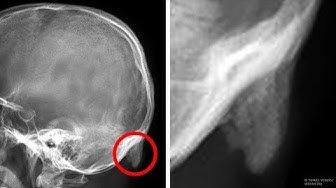

Apa yang biasanya kamu lakukan sambil menunggu bus atau duduk di kereta menuju kantor? Kalau kamu seperti banyak orang, kamu pasti sedang menonton layar ponsel pintar atau tablet. Kenapa tidak? Lagi pula, semua orang melakukannya. Gawai lebih dekat dengan kita dibandingkan apa pun atau siapa pun. Gawai adalah sumber informasi, komunikasi, dan kesenangan. Tapi perlu diingat bahwa kecanduan gawai berakibat buruk bagi tulang belakang. Ilmuwan Amerika menemukan bahwa kita melihat layar ponsel pintar lebih dari 2 jam sehari, dan menyentuhnya hampir 3.000 kali. Wah, bayangkan kumannya! Ilmuwan Australia melangkah lebih jauh dan meneliti bagaimana gawai memengaruhi kesehatan kita. Hasilnya mencengangkan... URUTAN WAKTU: Apa kuncup aneh di belakang kepala itu? 😮 0:41 Apakah itu berbahaya? 2:19 Apa itu "text neck"? 3:32 Gawai merugikan penampilanmu! 👈 5:24 Bagaimana cara mengurangi bahayanya? 6:19 Aplikasi keren untuk kesehatan 7:21 Kredit foto preview: Gambar sinar-X tengkorak: Oleh Tomas Vendis – https://ift.tt/2wjhJfH, CC BY 3.0 https://ift.tt/1mmxEyy, https://ift.tt/39iAr5N Animasi oleh Sisi Terang Berlangganan Sisi Terang https://www.youtube.com/channel/UCSg-Y9uI1E-my-I4WKKioEQ Musik oleh Epidemic Sound https://ift.tt/1NOjjY3 Materi stok (foto, rekaman, dan lain-lain): https://ift.tt/23rGg9b https://ift.tt/1eYTOMy https://www.eastnews.ru